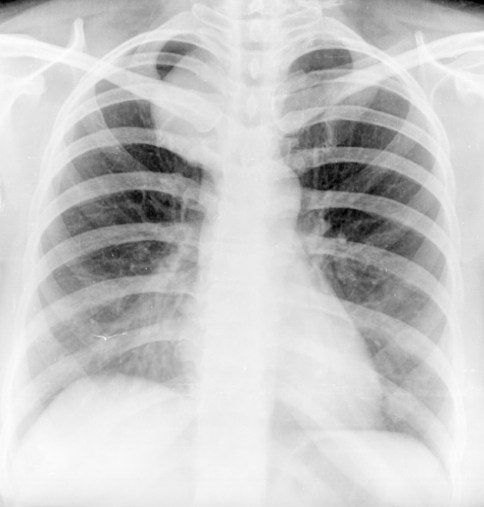

Frontal radiograph of the right hemithorax shows a relatively well defined approximately 2 cm sized oval soft tissue density nodule in the right middle zone. No calcification or cavitation. There is no other nodule. No effusion. No suspicious bone lesion.

Note that the description of the nodule should always include its shape (round/oval, spiculated, lobulated etc), and presence or absence of cavitation and calcification. Unless the nodule demonstrates certain findings consistent with a benign etiology, it should be labelled as indeterminate and should be further evaluated with a CT/biopsy.